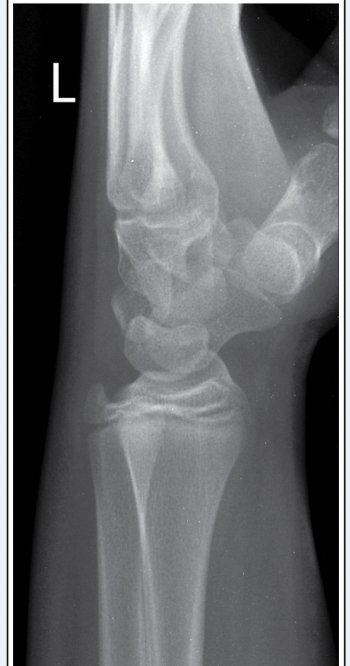

Which, from the following list of image criteria, is not met with this AP elbow image?

a.CR is not perpendicular with the IR

b.Hand is supinated

c.Equal demonstration of humerus and forearm

d.Arm is not extended

A